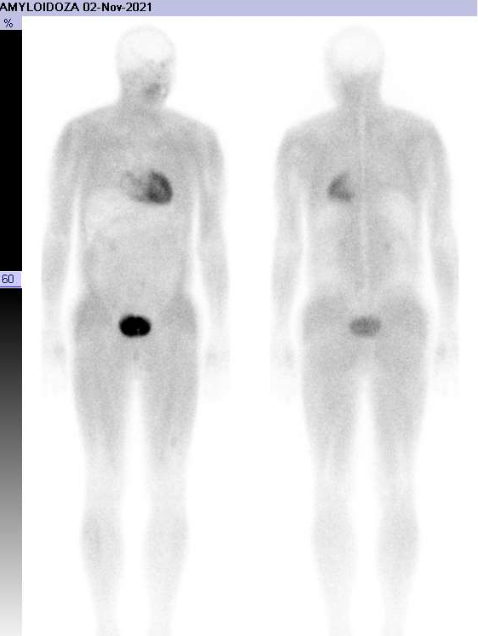

Badanie izotopowe

Badanie izotopowe SPECT stało się kluczową techniką w identyfikacji pacjentów z amyloidozą ATTR. W badaniu tym wykorzystuje się radioizotop technetu 99m w połączeniu ze znacznikami klasycznie stosowanymi w badaniu układu kostnego: jest to kwas 3,3-difosfo-no-1,2-propanodikarboksylowy (DPD) lub pirofosforan (PYP). Podczas badania izotopowego znacznik podaje się pacjentowi drogą dożylną i na podstawie odmiennego jego gromadzenia się w zdrowych i chorych partiach mięśnia serca dokonuje analizy uzyskanego w badaniu obrazu i potwierdza bądź wyklucza obecność amyloidozy.